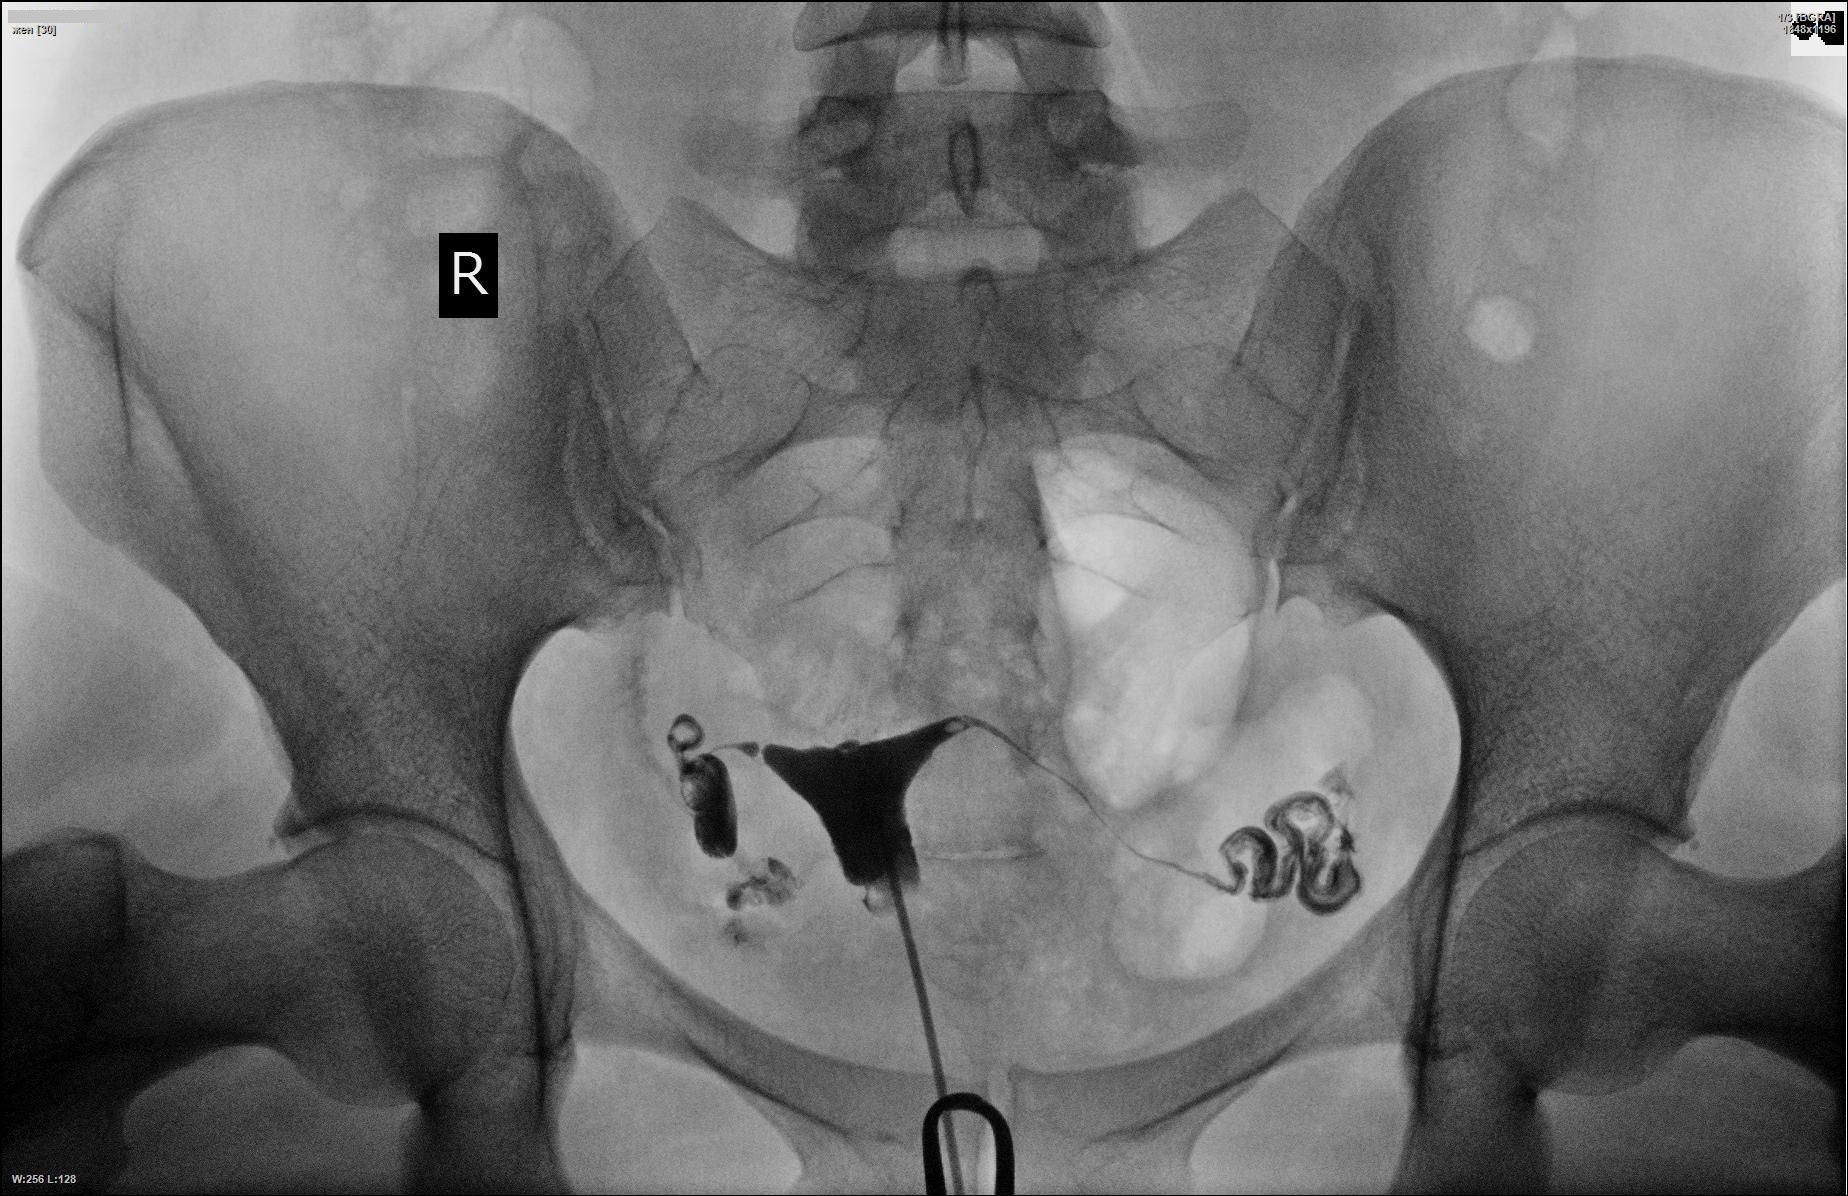

Медицинские снимки: Проходимость маточных труб

Раздел: Кадры-подсказки